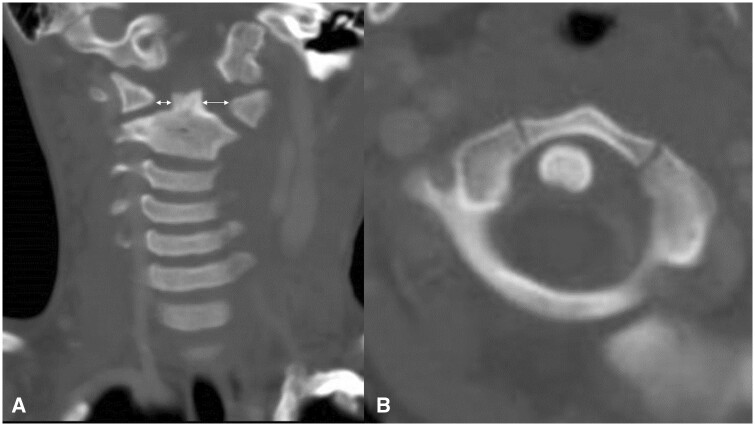

Various respiratory, musculoskeletal, gastrointestinal, neurological, and urinary complications have been reported in Kawasaki disease. Here, we describe a rare case of atlantoaxial rotatory fixation (AARF) associated with incomplete Kawasaki disease. The case is of a healthy 4-year-old Japanese boy who had a high-grade fever, lymphadenopathy, and torticollis diagnosed with incomplete Kawasaki disease. Intravenous high-dose immunoglobulin and oral aspirin quickly resolved his fever and improved his lymphadenopathy, but torticollis remained. On orthopaedic examination, torticollis was observed with a marked restriction of rotation, and an open-mouth anteroposterior cervical radiograph and a CT scan confirmed rotational dislocation at the dens axis (AARF). Cervical collar fixation was immediately started, and the torticollis gradually normalized within a week. AARF is defined as torticollis due to dislocation or subluxation of the atlantoaxial joint. The diagnosis of AARF is difficult with routine plain cervical radiographs in 2 directions alone, and an additional cervical open-mouth anteroposterior radiograph and a CT scan aid the diagnosis. AARF associated with Kawasaki disease is uncommon, and only 24 cases have been reported in the literature. AARF may occur in Kawasaki disease patients with cervical lymphadenopathy. Still, torticollis is often transient and may not be recognized or ignored by family doctors and paediatricians. Reduction of the atlantoaxial joint can often be achieved spontaneously or with conservative treatment such as a collar or neck traction, but treatment is difficult if the diagnosis is delayed. Therefore, family doctors and paediatricians need to suspect the onset of AARF if torticollis is observed during treatment for Kawasaki disease, perform plain cervical radiographs including open-mouth anteroposterior view and a CT scan of the cervical spine, and have orthopaedists immediately intervene to avoid invasive surgery.